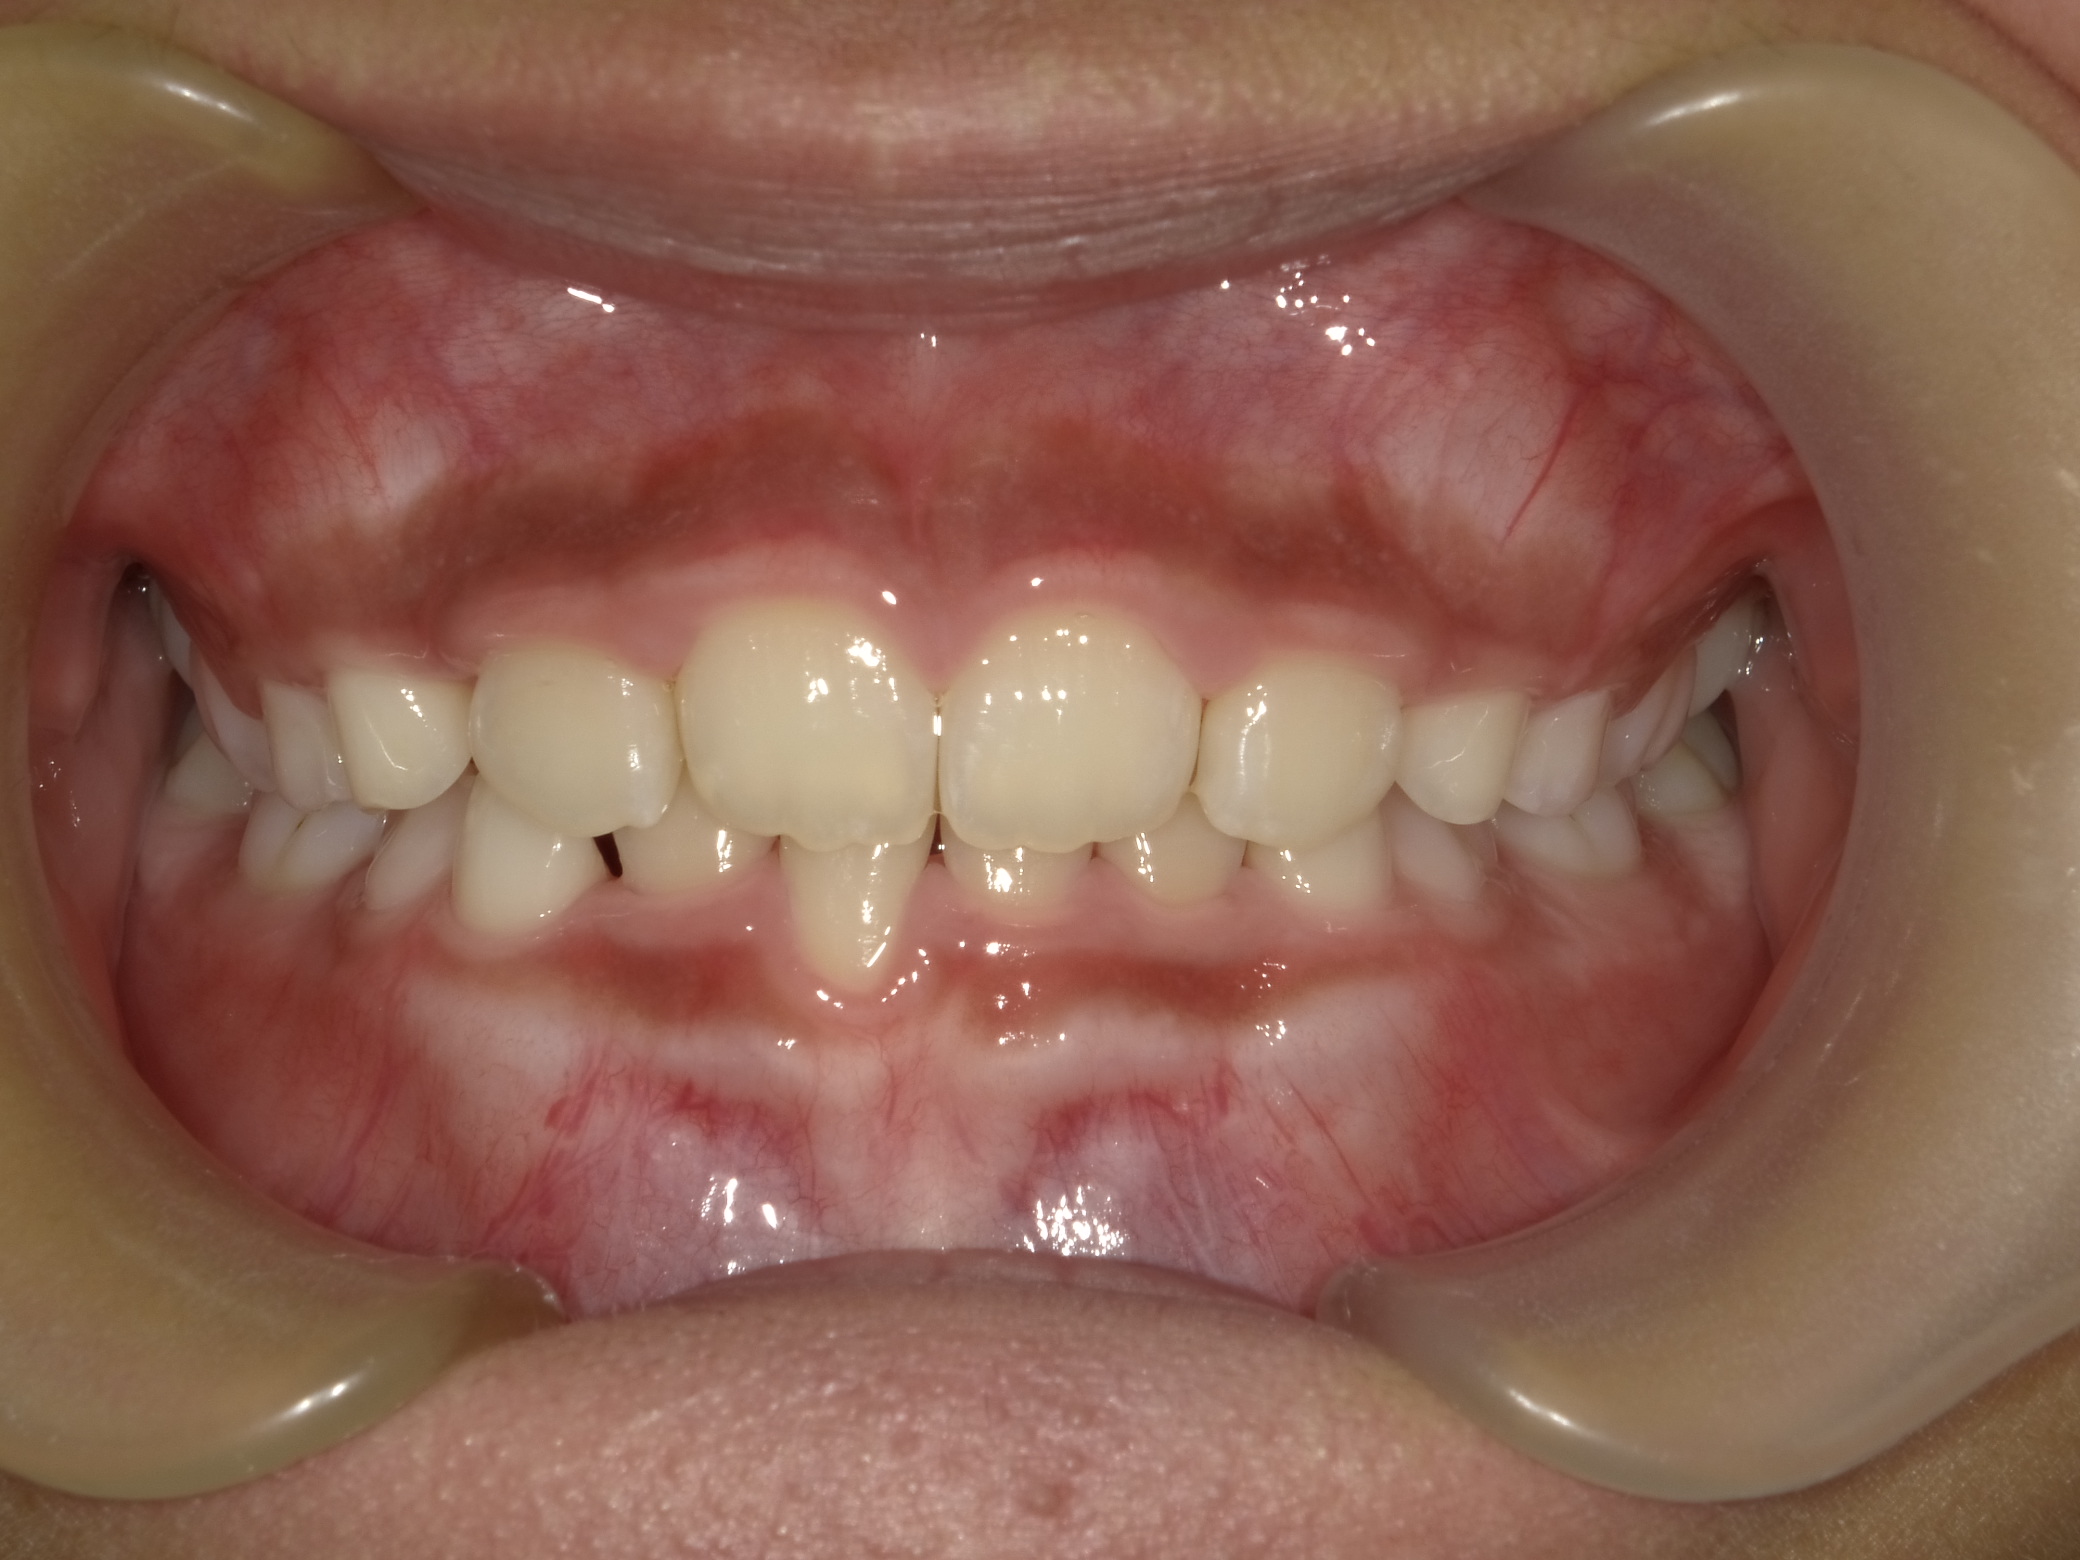

| 症例分類 | 交叉咬合 |

|---|---|

| 主訴 | 前歯がずれて咬んでいる |

| 年齢 | 9歳5ヶ月 |

| 性別 | 女性 |

| 抜歯部位 | なし |

| 使用装置 | 拡大装置、上顎前歯部のセクショナルアーチ装置、取り外し式保定装置 |

| 治療期間 | 1年2ヶ月 |

| 費用 | 相談料0円、検査料50,000円 動的矯正治療費330,000円 調整料6600円×15回分 保定装置料0円 |

| リスク・注意点 | 個々の歯の大きさに対して顎が小さく、歯が並ぶスペースが不足したために交叉咬合が生じています。これらを改善するために、幅の狭搾している歯列を側方に拡大した後、前歯を排列しました。

歯の動き方には個人差があり、予想された治療期間が延長する可能性があります。 治療中は矯正歯科装置が歯の表面に付いており、歯が磨きにくくなるため、むし歯や歯周病が生じるリスクが高まります。ハミガキを適切に行ってお口の中を常に清潔に保ち、さらに、かかりつけ歯科医に定期的に受診することが大切です。 矯正歯科装置の使用状況、定期的な通院など、矯正歯科治療には患者さんの協力が必要であり、それらが治療結果や治療期間に影響します。 治療の経過によっては当初予定していた治療計画を変更する可能性があります。 保定装置の装着時間が十分確保できない場合、歯並びや、咬み合せの「後戻り」が生じる可能性があります。 上下両側第二大臼歯の萌出を観察する必要があります。 |